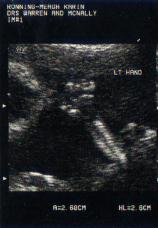

To the right is an image from Heloise's 12 week scan.

Heloise's 12 week scan We entered Heloise's pregnancy fully prepared. In early September 2001, I underwent a unique procedure called, a Trans-vaginal cervico-isthmic cerclage. This is a permanent buried stitch, like the rare and formidable abdominal stitch, but surgically placed via the vagina rather than the abdomen. It loops through the ligaments on either side of the cervix, holding the cervix closed. It is intended to remain permanently in place through several pregnancies. We fell pregnant the following cycle, our due date being 15 July, 2002, with a planned Cesarean section scheduled the end of June. We hoped that with the aid of this cerclage, we would deliver a full-term baby.

All was going extremely well, with only a short episode of bleeding at around 12 weeks, the cause of which went unknown. We carried on, following our protocol of limited activities and rest. I ate well, rested much, and never lifted a finger. Kieron did all the work. We hoped our efforts would make a difference.